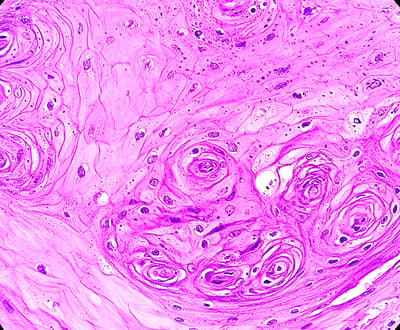

- Pathology (1)